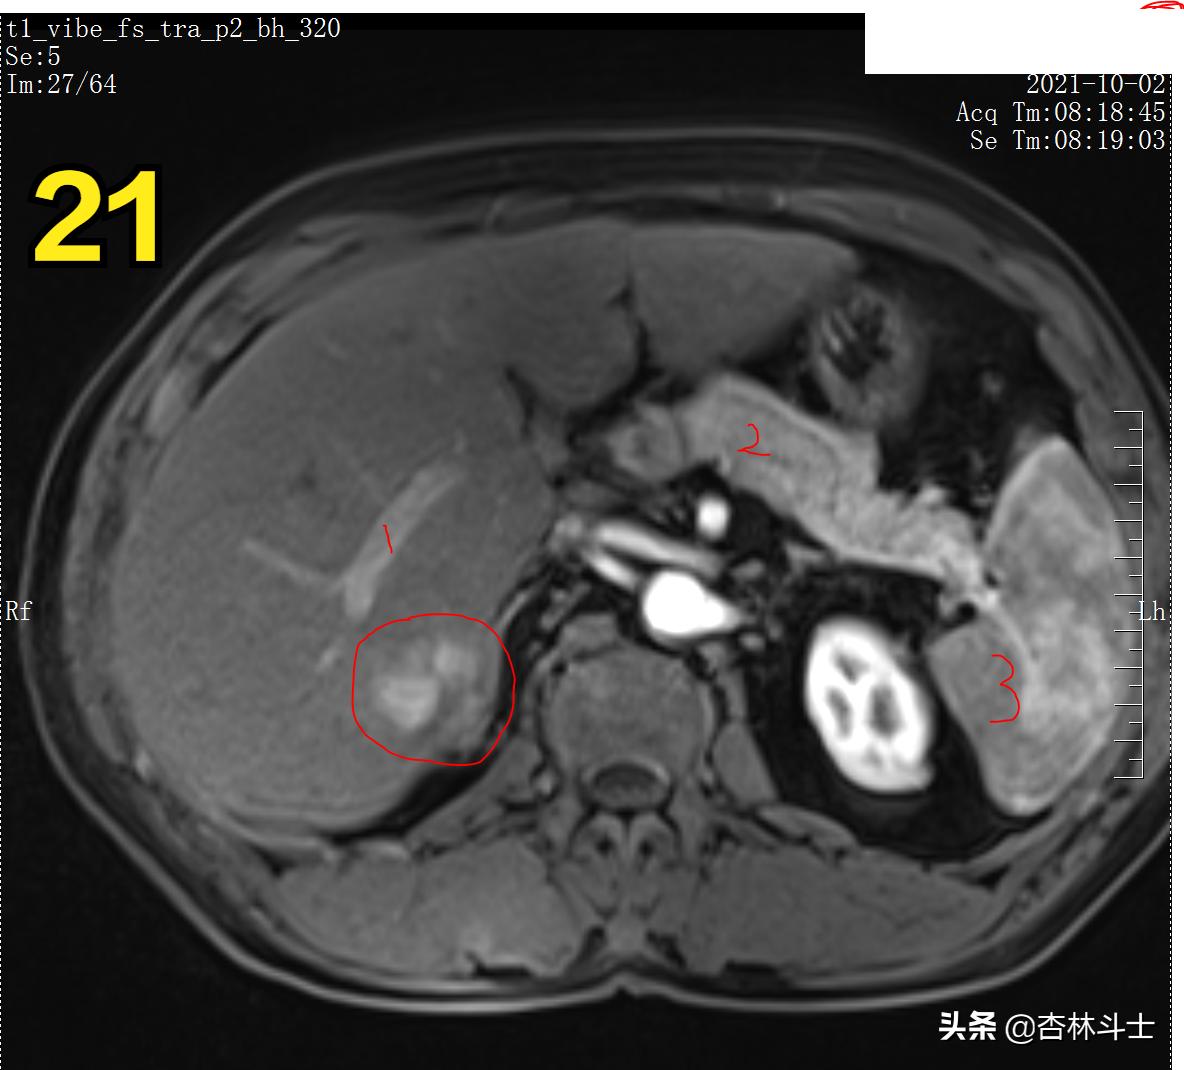

T1压脂动脉期 1、门静脉右支 2、胰腺 3、脾

T1压脂动脉期

图21、22 动脉期病灶明显强化